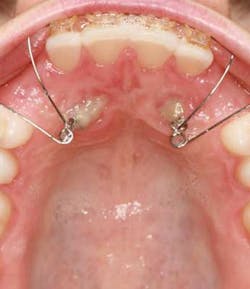

A ballista appliance was used to prevent a facial pull of the canines in order to avoid and prevent resorption of the roots of the lateral incisors. As movement progressed over the course of the next year, eruption of the canines was considered a success. Once in position, they will be pulled facially into occlusion.

The patient is pleased with the progress reached thus far and is ecstatic at the anticipation of a successful outcome.